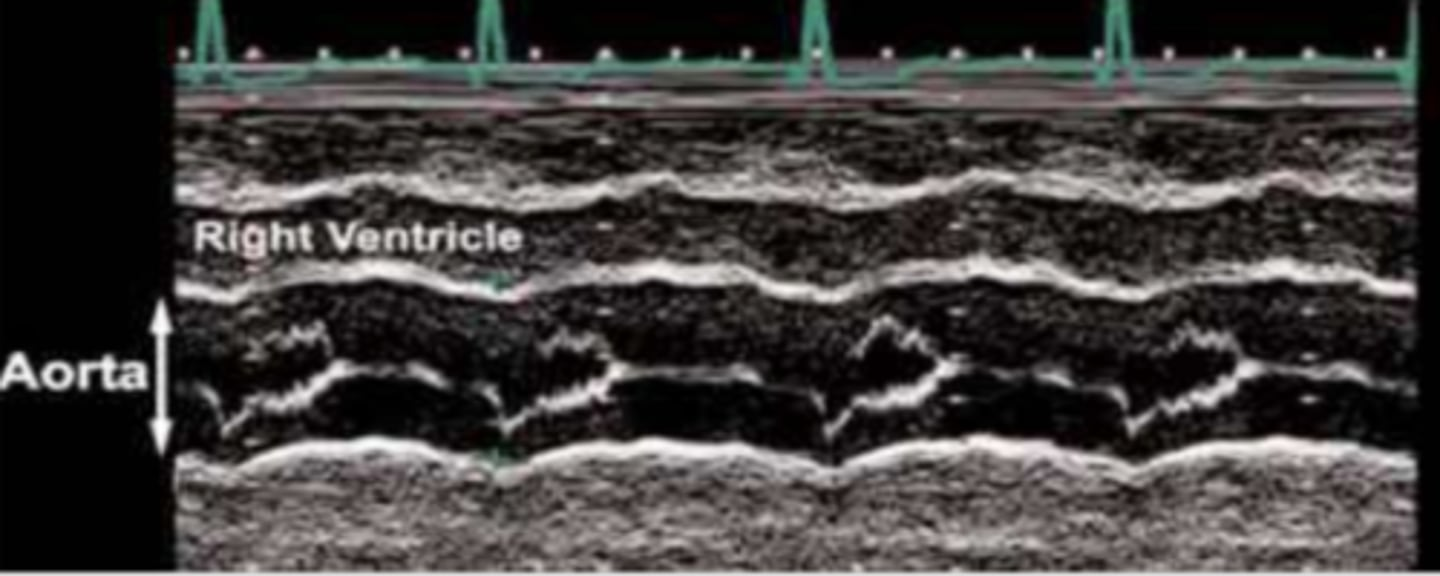

consistent with dyskinetic wall motion and appears as D-shaped septum in PAP view

right ventricular volume overload (RVVO)